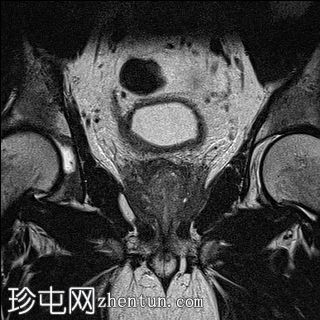

冠状位

T2加权像

外周带 (PZ):

T2WI:双侧外周带弥漫性、不均匀低T2信号,范围>15 mm,尖端后内侧可见小片相对保留的病灶。左侧尖端及腺体中部可见包膜隆起。评分5/5。

DWI/ADC:高b值DWI呈弥漫性高信号,ADC呈相应低信号(扩散受限)。评分5/5。

DCE:早期强化阳性。

PI-RADS:5 - 极高风险(极有可能存在临床意义的癌症),考虑炎症性病变。

肉芽肿性前列腺炎是多参数磁共振成像 (mpMRI) 中一种重要的、与临床意义显著的前列腺癌相似的疾病,因为它可以产生明显的周围带异常,伴有扩散受限和早期强化,通常导致较高的 PI-RADS 分级。

在本病例中,mpMRI 显示双侧周围带弥漫性 T2 低信号,高 b 值 DWI/ADC 图像上呈扩散受限,早期强化阳性,并伴有包膜轮廓隆起。这种影像学表现可能类似于浸润性或广泛性周围带癌,尤其是在 PSA 升高和直肠指检异常的情况下。然而,炎症性疾病,特别是肉芽肿性前列腺炎,可能出现类似的影像学表现。经直肠前列腺活检的组织病理学检查显示,患者患有严重的慢性非干酪性肉芽肿性前列腺炎,未见肿瘤证据。